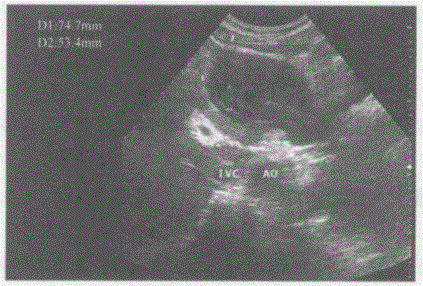

问题 临床资料:女,34岁,自述进食后上腹部不适。 超声综合描述:腹主动脉下腔静脉前方可见10.1cm×9.3cm形态不规则低回声,边界清晰,内回声不均匀,肝左叶受其推挤形态失常。 超声提示:

选项 A.胰腺癌 B.胃平滑肌肉瘤 C.肝癌 D.腹腔肿大淋巴结

答案 B